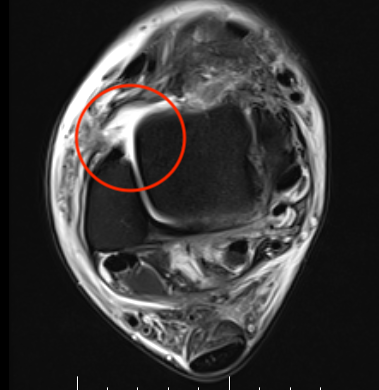

MRI

Torn ATFL

CFL